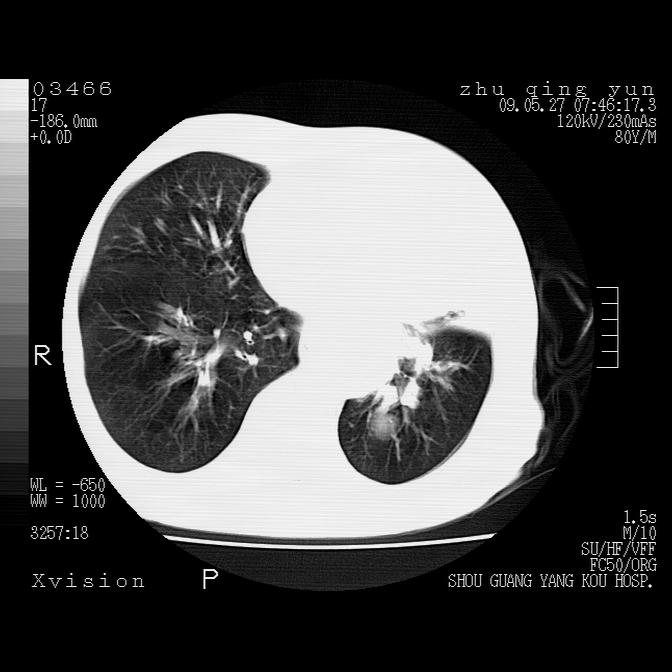

病人男性,年龄80,气喘来院,其他病史不太详细,1月前有过恶心,呕吐,在当地人民医院做过钡餐,诊断胃炎,

1)考虑左肺中央型肺癌并阻塞性肺炎,后下纵隔受侵伴纵隔淋巴结转移。2)双侧少量胸腔积液,胸膜增厚。3)心包积液。

左肺下叶见多发片状及结节状病灶,左肺基底段支气管闭塞,纵隔内见多发淋巴结肿大,纵隔向左侧移位,左侧胸廓变小。应该是左肺下叶中心型肺癌,纵隔淋巴结转移,左侧肺内转移,左肺基底段肺不张,阻塞性肺炎。

1)考虑左肺中央型肺癌并左肺下叶阻塞性肺炎、不张;左胸膜腔积液、心包积液、纵隔淋巴结转移;癌肿累及左心房。2)左心室大。冠状动脉壁钙化斑。

支持以上,左肺肿块应该是周围型吧,考虑左下肺周围型肺癌伴肺内转移,阻塞性肺炎,纵隔淋巴转移,左侧胸膜及心包转移